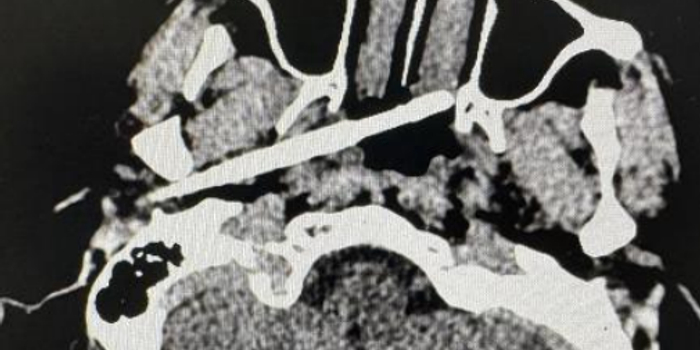

筷子从外耳道上方插入,穿透侧颅底-咽旁间隙,直抵鼻咽部,筷子尖端距离颈内动脉仅5毫米……1月10日,患者陈先生经紧急转诊至珠江医院,创伤中心迅速开启手术“绿色通道”,启动多学科会诊,经耳鼻咽喉头颈外科中心于超生主任医师团队2小时手术,最终顺利取出这双夺命的筷子。

东莞45岁男子在与人争执时,一根筷子从耳部插入颅底,筷子被折断,断端残留体内。更令人揪心的是,筷子不仅穿透了耳部骨质,筷子尖端距离颈内动脉仅5毫米——这是大脑供血的主干线之一,一旦破裂,可导致瞬间大出血死亡。

“筷子穿透路径紧贴咽鼓管旁的颈内动脉水平段,必须警惕迟发性假性动脉瘤等继发风险。”经多学科深入讨论,制定了“内镜联合开放手术”方案。手术安排在复合手术室进行,如不慎出现颈内动脉损伤破裂大出血,脑血管外科可迅速介入,植入支架控制出血,为安全取出异物提供双重保障。